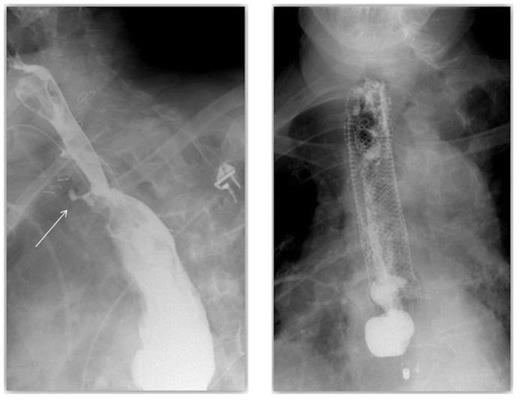

On post-operative day 7 a routine post-operative contrast swallow was performed. This identified a spill of contrast due to a 5mm anterior defect at the level of the oesophago-gastric anastomosis suggestive of focal ischaemia. This was managed with washout and drainage and a covered oesophageal stent. A further contrast swallow revealed contrast aggregating around the drain (Figure 1) and that the covered oesophageal stent was appropriately positioned with no evidence of on-going leak (Figure 2).

A contrast swallow demonstrating contrast aggregating around the drain & A covered oesophageal stent appropriately positioned with no evidence of leak